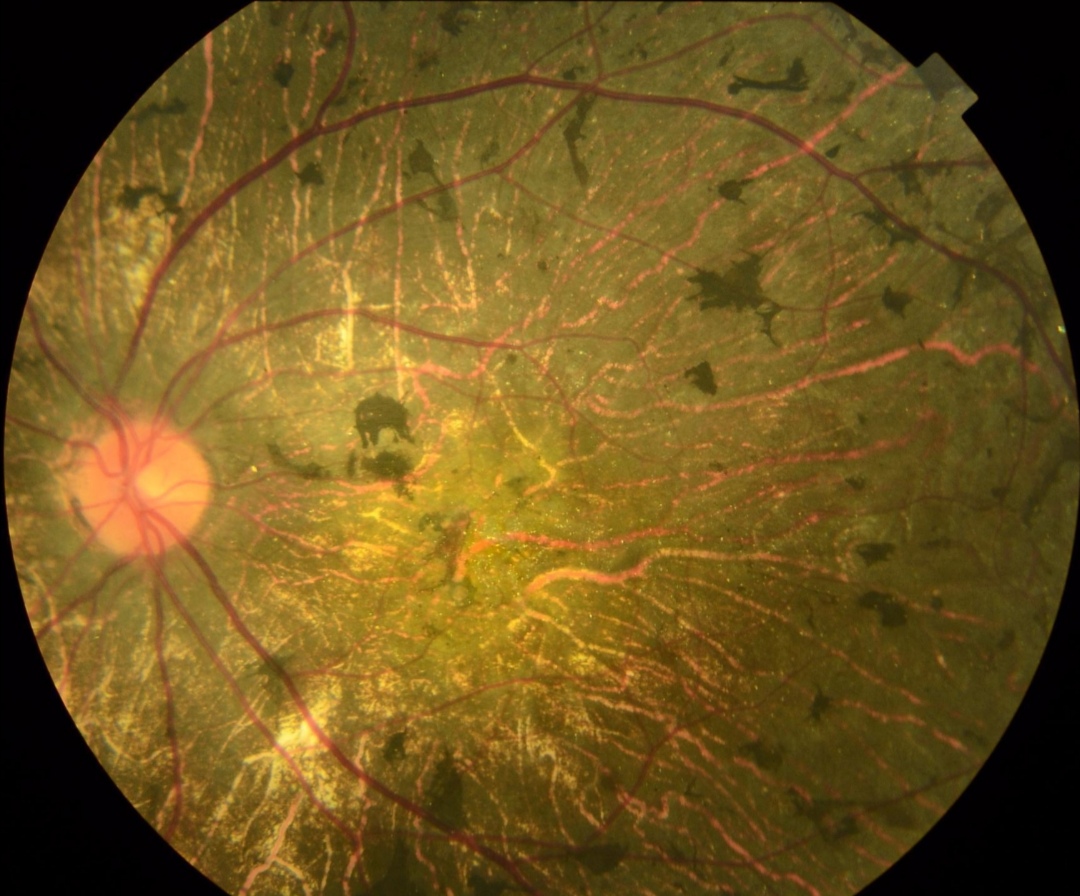

视网膜色素变性眼底图